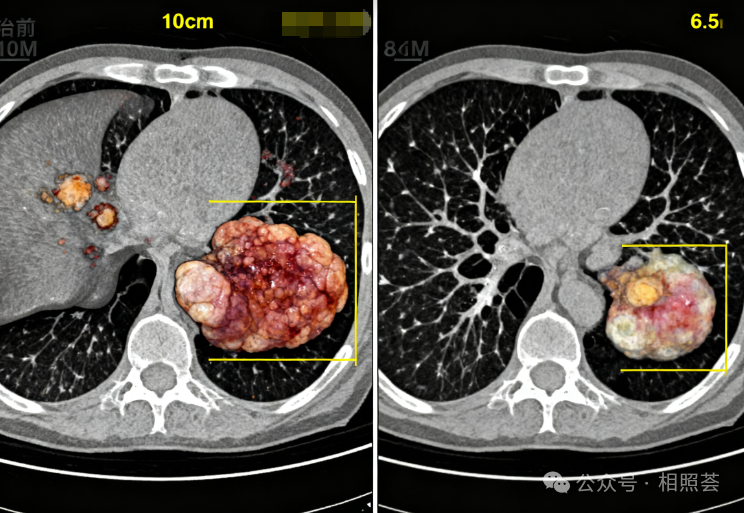

【TCR-T治疗案例分享】从“判刑3个月”到“带瘤生存”:肝癌父亲用TCR-T争取了5年!

“爸,今天复查结果出来了,医生说肿瘤又小了一点!”2025年10月,当女儿小林(化名)举着CT报告冲进病房时,47岁的李先生正望着窗外飘落的银杏叶。五年前,医生曾断言他“活不过3个月”,而如今,这个曾被肝癌判了“死刑”的男人,不仅见证了女儿结婚生子,更用亲身经历改写了晚期肝癌的治疗结局。。01肝癌晚期,生命进入倒计时2020年3月,李先生因持续腹痛、黄疸加重入院检查,最终确诊为晚期乙肝相关性肝细胞